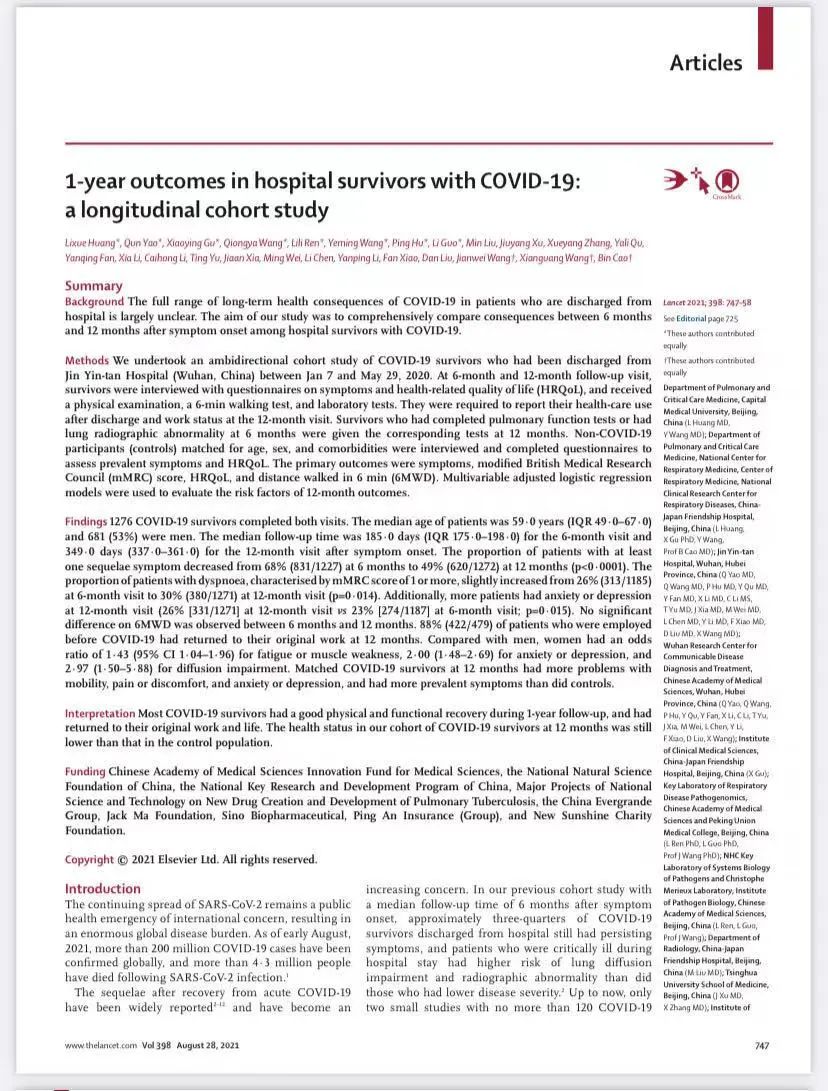

1.至2021年9月1日 , 新冠疫情在全球导致了2.18亿人感染和452万人死亡 , 据估计全球有近10%左右的新冠康复者患有不同的新冠后遗症 。 据《柳叶刀》最新研究 , 2020年初曾在武汉金银潭医院住院的1276名新冠病人 , 在出院12个月后仍有肌无力/疲倦、抑郁/焦虑、呼吸困难、睡眠困难、脱发、关节痛等主流的后遗症 。

2.研究显示 , 虽然新冠患者的症状在半年有了改善 , 但出现呼吸困难、焦虑抑郁的患者比例变大 。 此外 , 与SARS后遗症类似 , 疲劳或肌无力也是新冠患者最常见的症状 。 但该研究也有诸多局限性 , 需要持续的纵向随访 。

随着COVID-19大流行病在全球范围内的持续存在 , 医学上新出现的挑战是从应对急性感染转向应对新冠长期后果对医疗体系造成的负担 。 全球据估计有近10%左右的新冠康复者患有不同的新冠后遗症 , 据国家卫健委官方网站8月31日数据 , 国内累计报告确诊病例94879例 , 死亡病例4636例 。 治愈出院病例89145例 。 这89145例确诊治愈出院病例中有多少人患有新冠后遗症 , 他们的康复情况如何?这些新冠后遗症有那些症状?8月28日 , 国际著名医学杂志《柳叶刀》上发布了一项关于国内新冠患者后遗症的新研究 。 这是目前最大型的、时间长达一年的随访 , 评估了2020年初曾在武汉金银潭医院住院的1276名新冠病人 , 在出院后12个月的健康状况 , 对国内新冠后遗症患者的情况 , 提供了最新的数据 。 这篇论文显示 , 这1276名新冠患者出院出院12个月后 , 仍有:—30%呼吸困难—26%抑郁/焦虑—12%没有回到病前的工作 。 国外新冠后遗症的症状共有205个 , 中国共有多少个?这篇论文显示:肌无力/疲倦、抑郁/焦虑、呼吸困难、睡眠困难、脱发、关节痛等 , 是目前为止随访患者较为主流的后遗症 。 新冠病后的疲劳或肌无力看上去无足轻重 , 实际上它是慢性的长期的疲倦 , 不少人还有劳累后不适的现象 , 即体力或者脑力消耗后症状会恶化 , 严重影响患者的生活 , 有的人因此不能工作、或不敢出门 。 另据这篇研究文章的相关数据 , 如果把排除的56位有精神问题/痴呆症而不能参加随访的患者也部分考虑在内的话 , 那有精神症状的人群比例其实更高 。